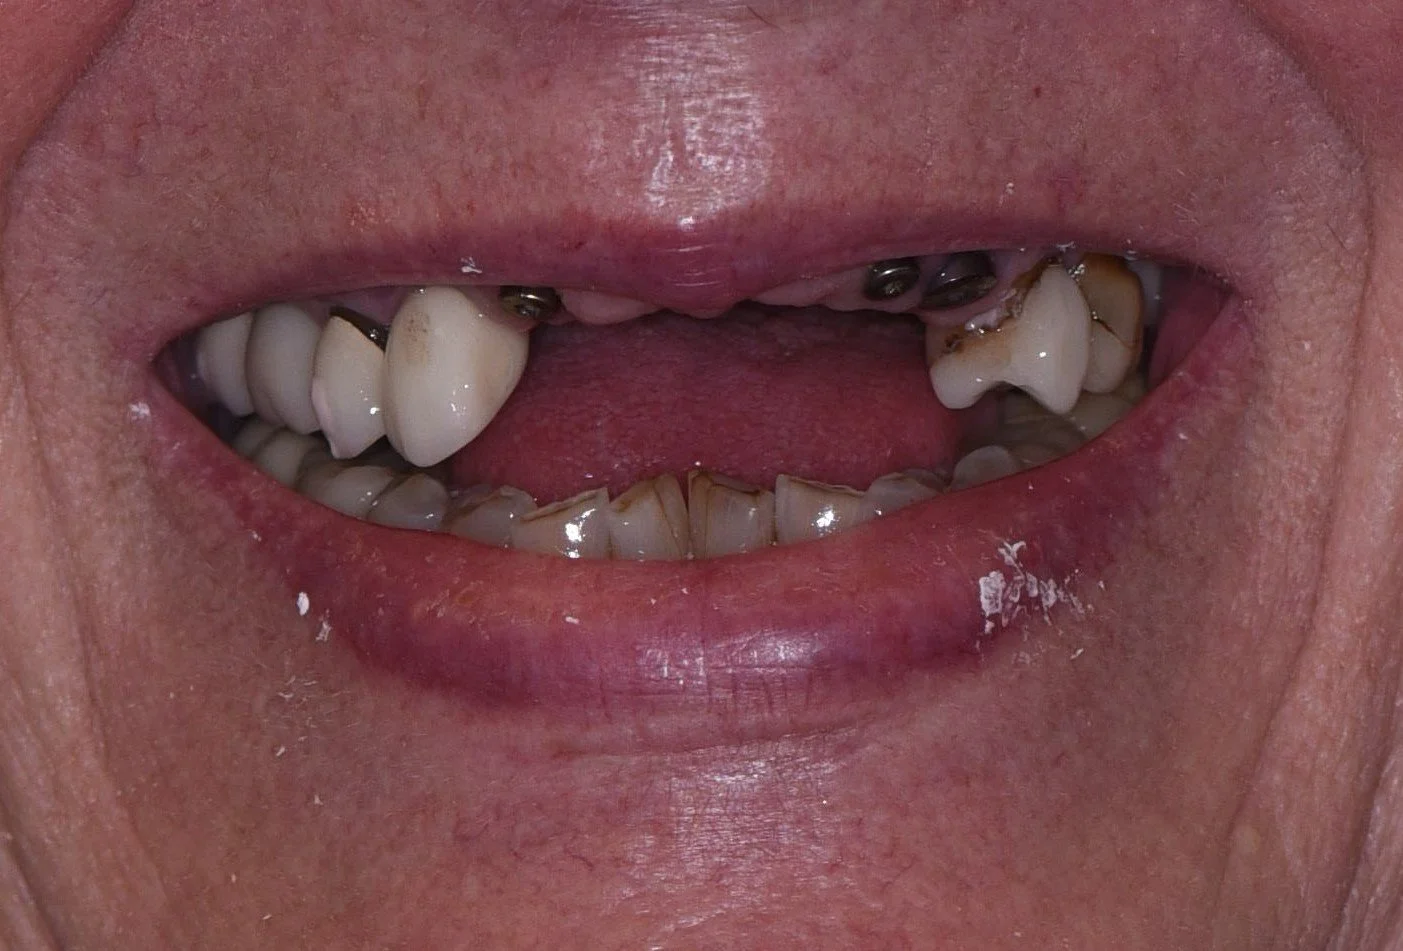

Before